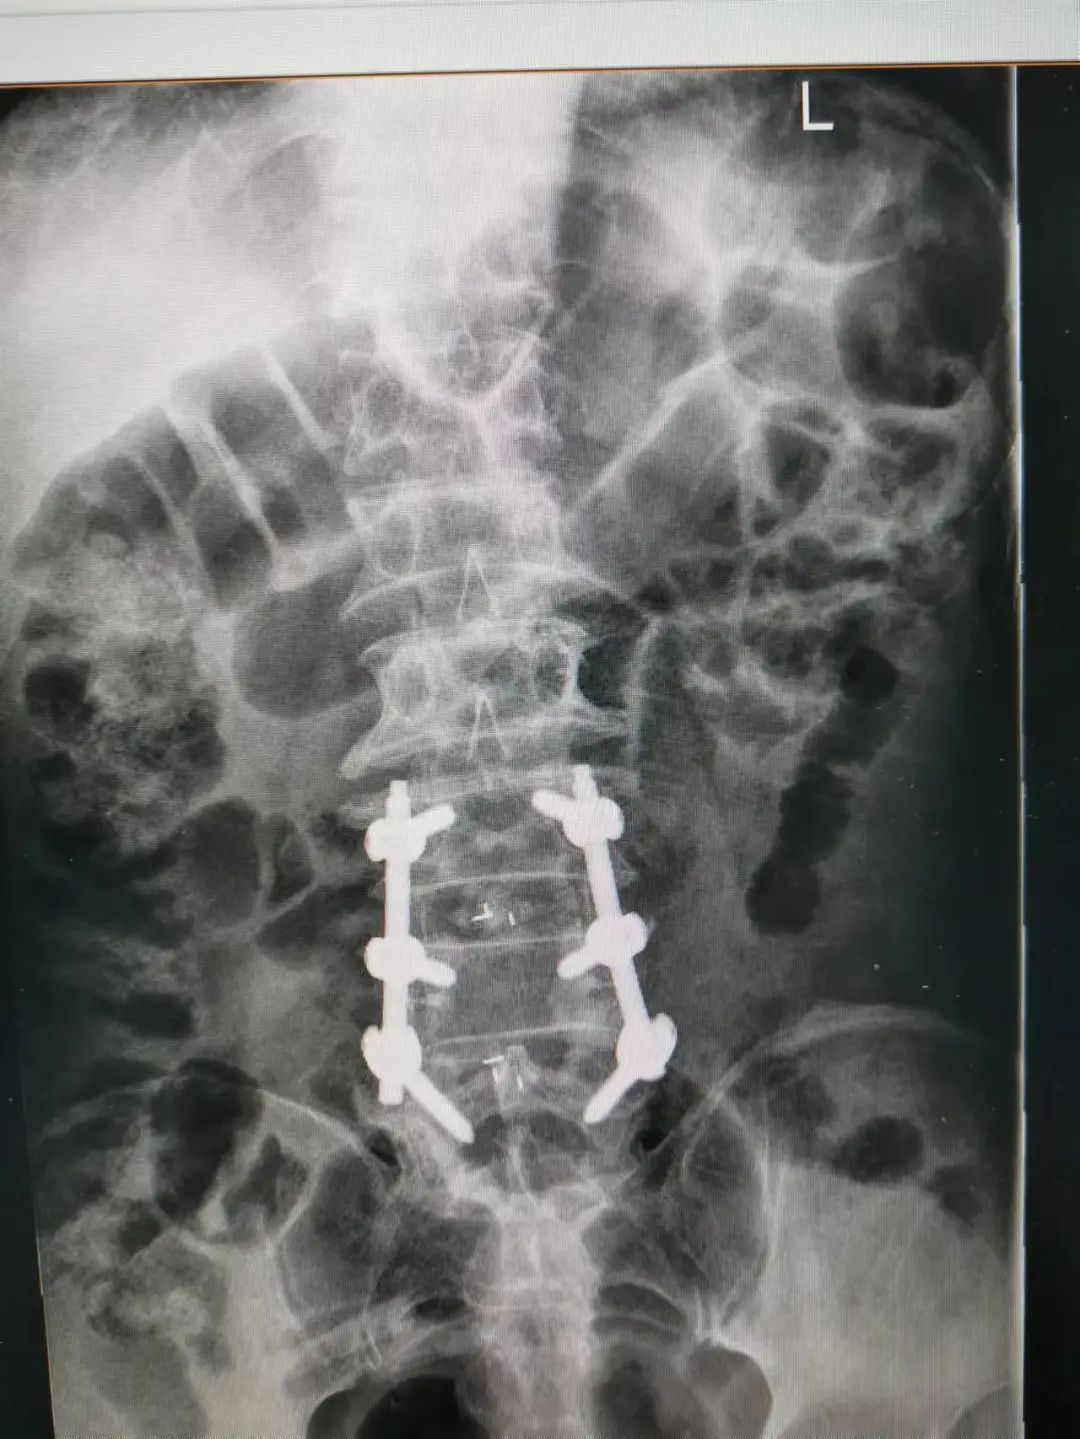

楊先生腰椎管狹窄癥拍片

由于楊先生的病情嚴重,需住院治療。楊先生入院后,瀘州市中醫(yī)醫(yī)院骨傷二科科主任楊陳一制定了手術計劃,決定脊髓型頸椎病的手術從前路切開減壓,頸3/4 、頸4/5、 頸5/6、 頸6/7椎間盤切除,椎間融合,鋼板內固定術手術,而腰椎管狹窄癥經后路切開減壓,腰3/4、腰4/5椎同盤動除,椎間融合、釘棒系統(tǒng)內固定術。

楊先生術后拍片